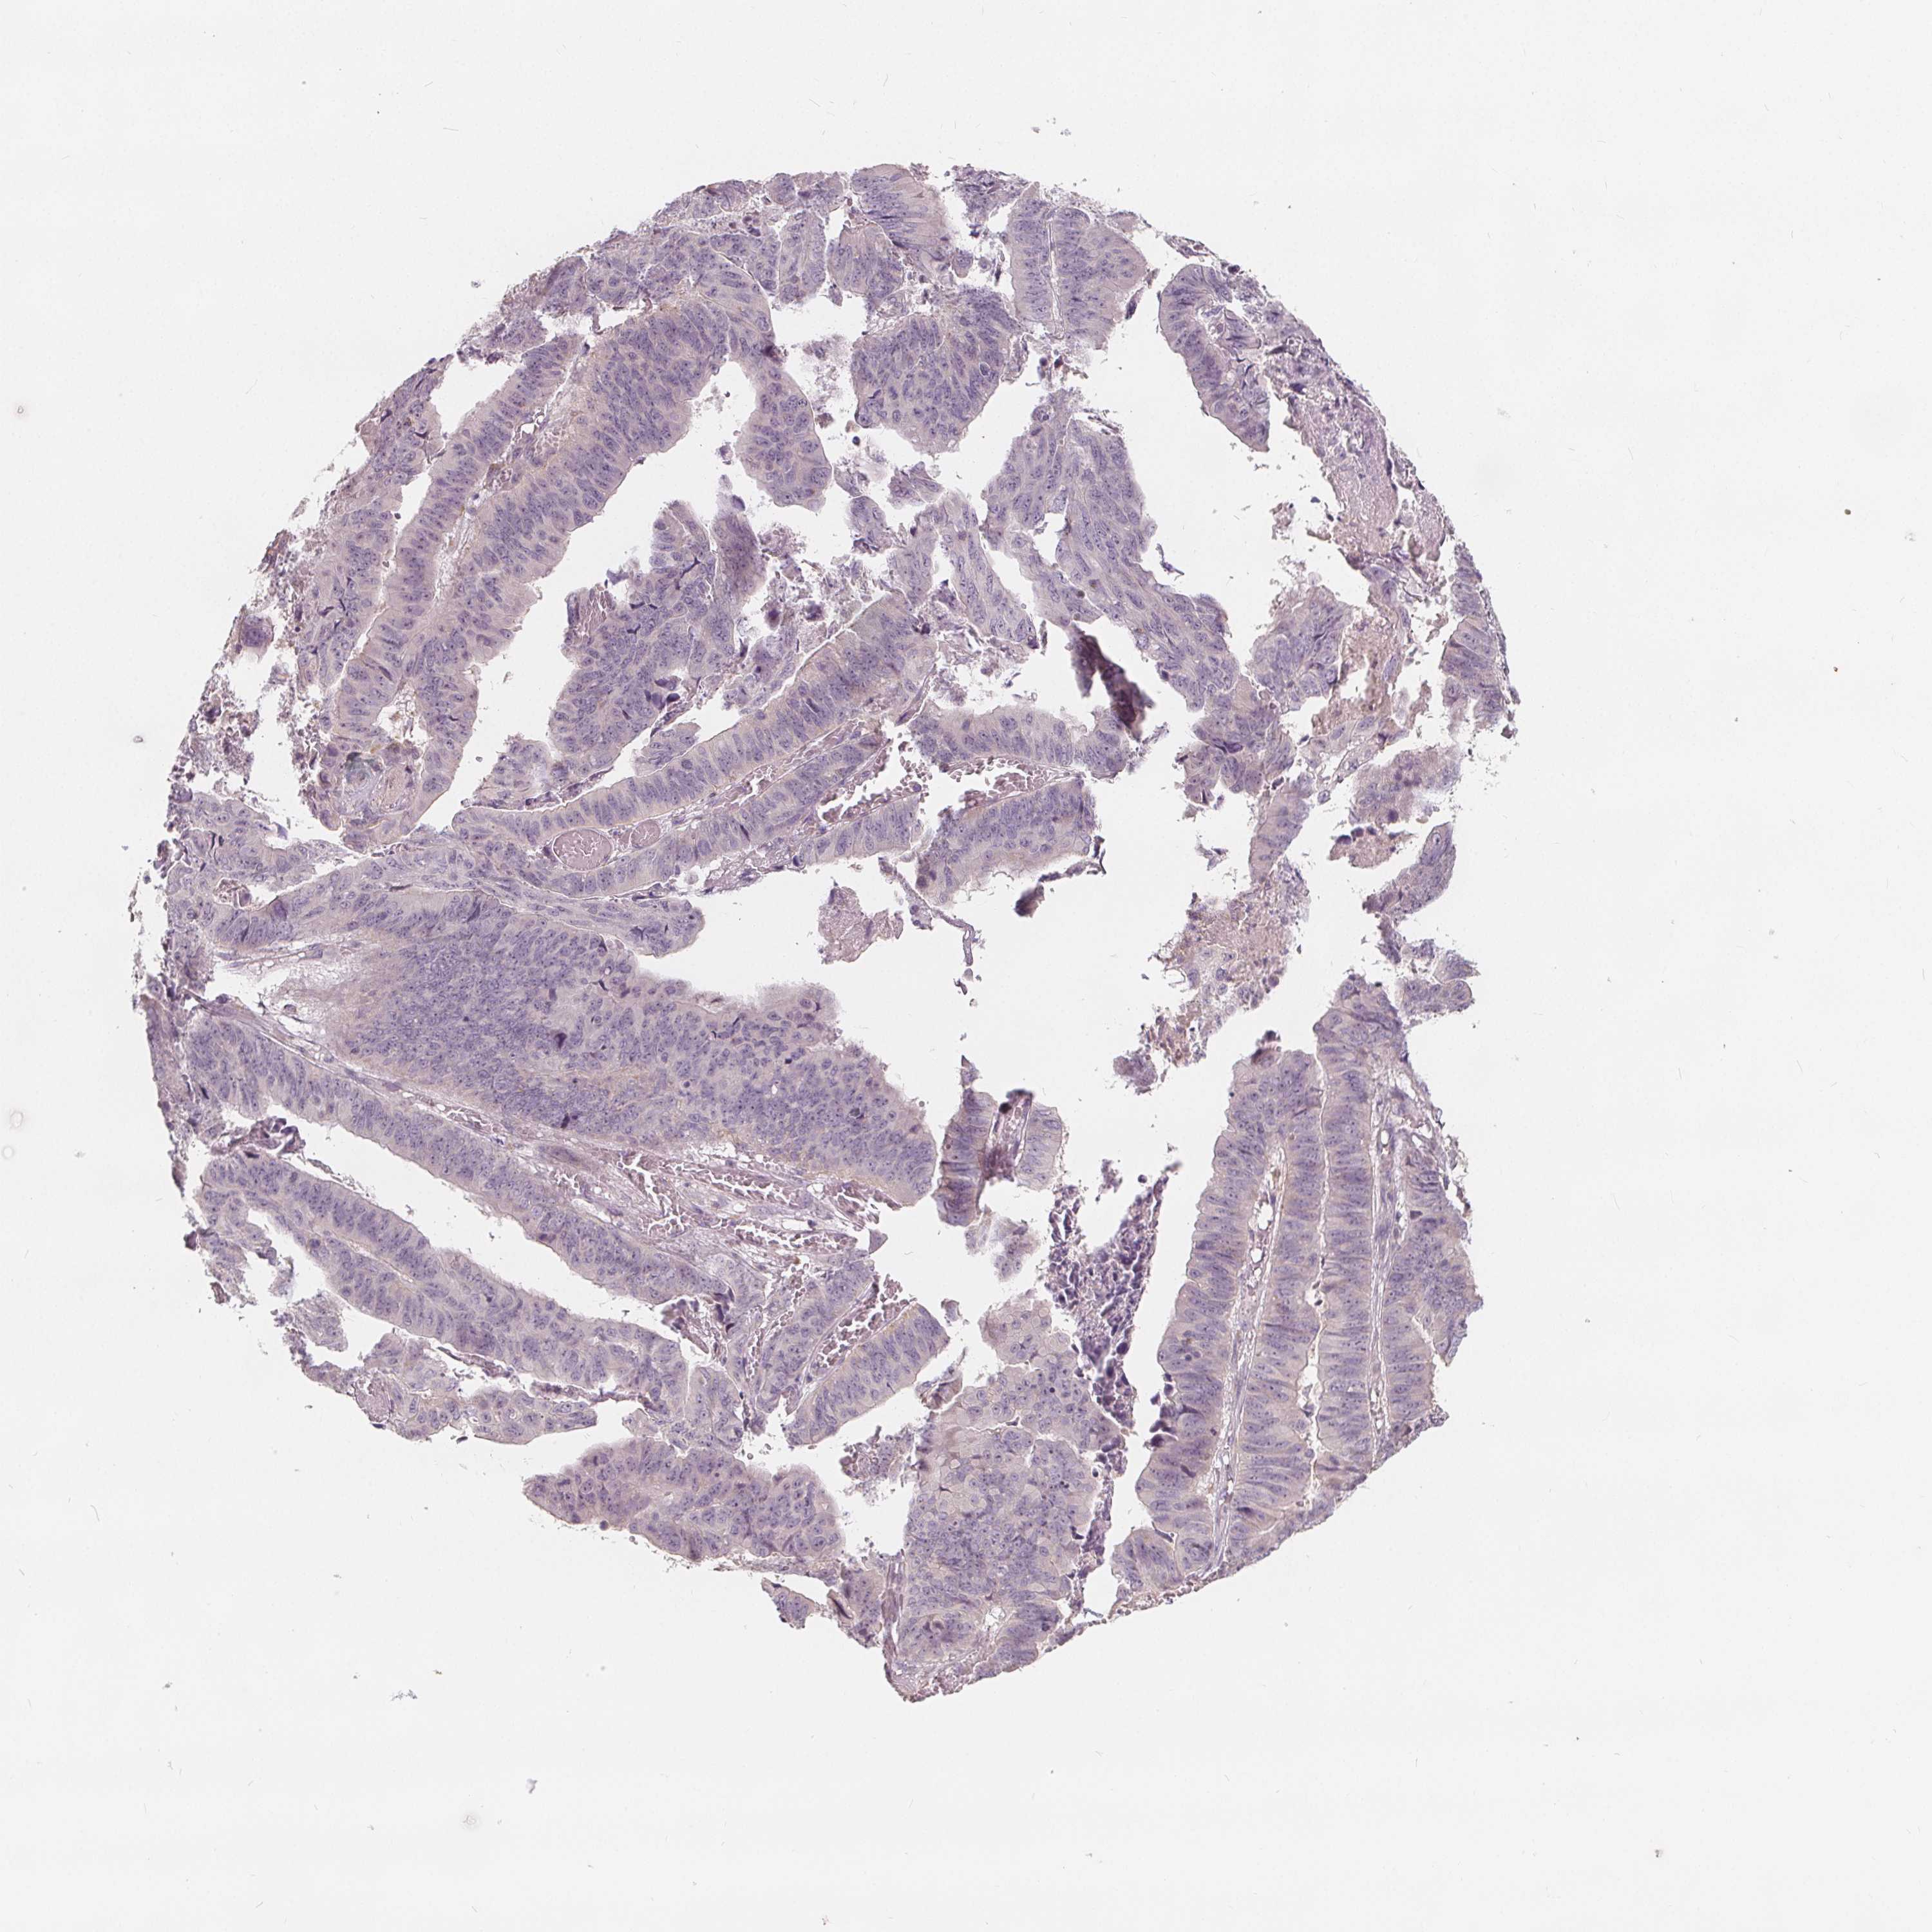

STOMACH CANCER - Protein expressioni

A mouse-over function shows sample information and annotation data. Click on an image to view it in a full screen mode. Samples can be filtered based on level of antibody staining by selecting one or several of the following categories: high, medium, low and not detected. The assay and annotation is described here.

Note that samples used for immunohistochemistry by the Human Protein Atlas do not correspond to samples in the TCGA dataset.

Antibody stainingi

Antibody staining in the annotated cell types in the current human tissue is reported as not detected, low, medium, or high, based on conventional immunohistochemistry profiling in selected tissues. This score is based on the combination of the staining intensity and fraction of stained cells.

Each image is clickable and will lead to virtual microscopy that enables deeper exploration of all samples and also displays staining intensity scores, fraction scores and subcellular localization as well as patient and tissue information for each sample.

Antibody HPA036040

Antibody HPA036041

Staining

High

Medium

Low

Not detected

Intensity

Strong

Moderate

Weak

Negative

Quantity

>75%

75%-25%

<25%

None

Location

Nuclear

Cytoplasmic/membranous

Cytoplasmic/membranous,nuclear

Adenocarcinoma, NOS